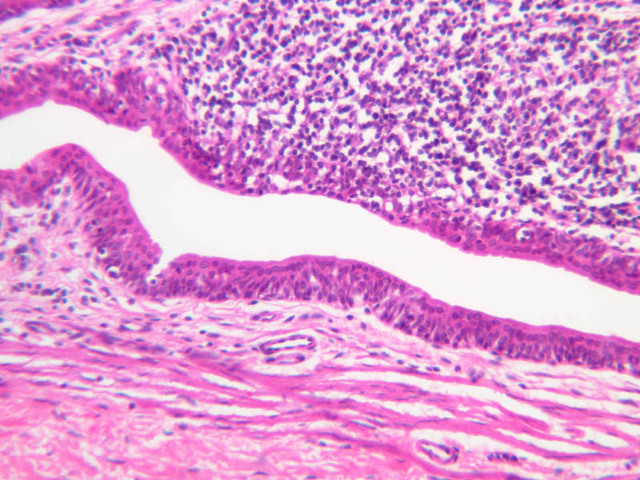

Continuous capillaries consist of a sheet of endothelial cells that, as the name implies, has no defects or discontinuities. Fenestrated capillaries have areas of fusion of plasmalemmae that are responsible for enhanced transport as in kidney and endocrine organs. Discontinuous capillaries, or sinusoids, have gaps between individual endothelial cells. Sinusoids of the liver and spleen are examples. Sinusoids, which occur in some organs as branches directly from arterioles (in place of capillaries) also consist of a single layer of endothelial cells, but are two to three times greater in diameter and more irregular in shape than capillaries. Many of the cells lining sinusoids have phagocytic capabilities (e.g. Kupffer cells of the liver). Venules, the vessels into which capillaries or sinusoids feed and the smallest vessels of the venous system are endothelial tubes, larger in diameter than capillaries, surrounded by a thin sheath of connective tissue cells and fibers. When venules reach a diameter of about 40 μmμ, smooth muscle cells appear, but do not form a distinct layer. Look for arterioles, capillaries, and venules in slides B-12 (jejunum, H&E [10x, 20x, 40x-labeled] [2.5x, 10x, 20x, 40x]), B-13 (jejunum, PAS [2.5x, 10x, 20x-labeled, 40x]), B-15 (jejunum, H&E [2.5x, 10x, 20x, 40x] [2.5x, 10x, 20x, 40x] [10x, 20x, 40x]), B-16 (ileum, H&E [10x, 20x, 40x-labeled] [2.5x, 10x, 20x, 40x]), B-23 (colon, H&E [2.5x, 10x, 20x-labeled, 40x]), B-24 (colon, H&E [2.5x, 10x, 20x, 40x-labeled]), B-26 (rectal-anal junction, H&E [2.5x, 10x, 20x, 40x] [2.5x, 10x, 20x, 40x-labeled]). Capillaries and venules may be distinguished from small lymph vessels, also present, by the fact that the blood vessels contain red blood cells while the lymph vessels do not. Study a number of examples of each kind of small vessel, looking for the changes that characterize arterioles as they get smaller and venules as they get larger. Be able to distinguish differences between capillaries and the smallest arterioles and venules. Look for additional examples of small vessels of the various kinds in the dense connective tissue of skin (A-48, abdominal [2.5x, 10x, 20x, 40x]; A-50, fingertip [2.5x, 10x, 20x, 40x] [2.5x, 10x, 20x, 40x] [2.5x, 10x, 20x, 40x]; A-58, axillary [2.5x, 10x, 20x, 40x-labeled]), using care not to confuse the cross-sections of glands (which consist almost entirely of epithelial cells) with blood vessels. Arterioles, especially, are cut in different planes and are not always easy to identify.

The structure of sinusoids can be studied in the liver (B-29, H&E [10x, 20x, 40x] [10x-labeled, 20x, 40x-labeled]; B-30, H&E [10x, 20x, 40x]; B-35, PAS [10x, 20x, 40x]) where they occur as endothelial tubes between plates of hepatocytes. In the liver, they are channels slightly larger in diameter than red blood cells and the individual lining cells have open spaces between them. The principal difference between sinusoids and capillaries is size, which presumably allows blood to flow more slowly in the larger sinusoids.